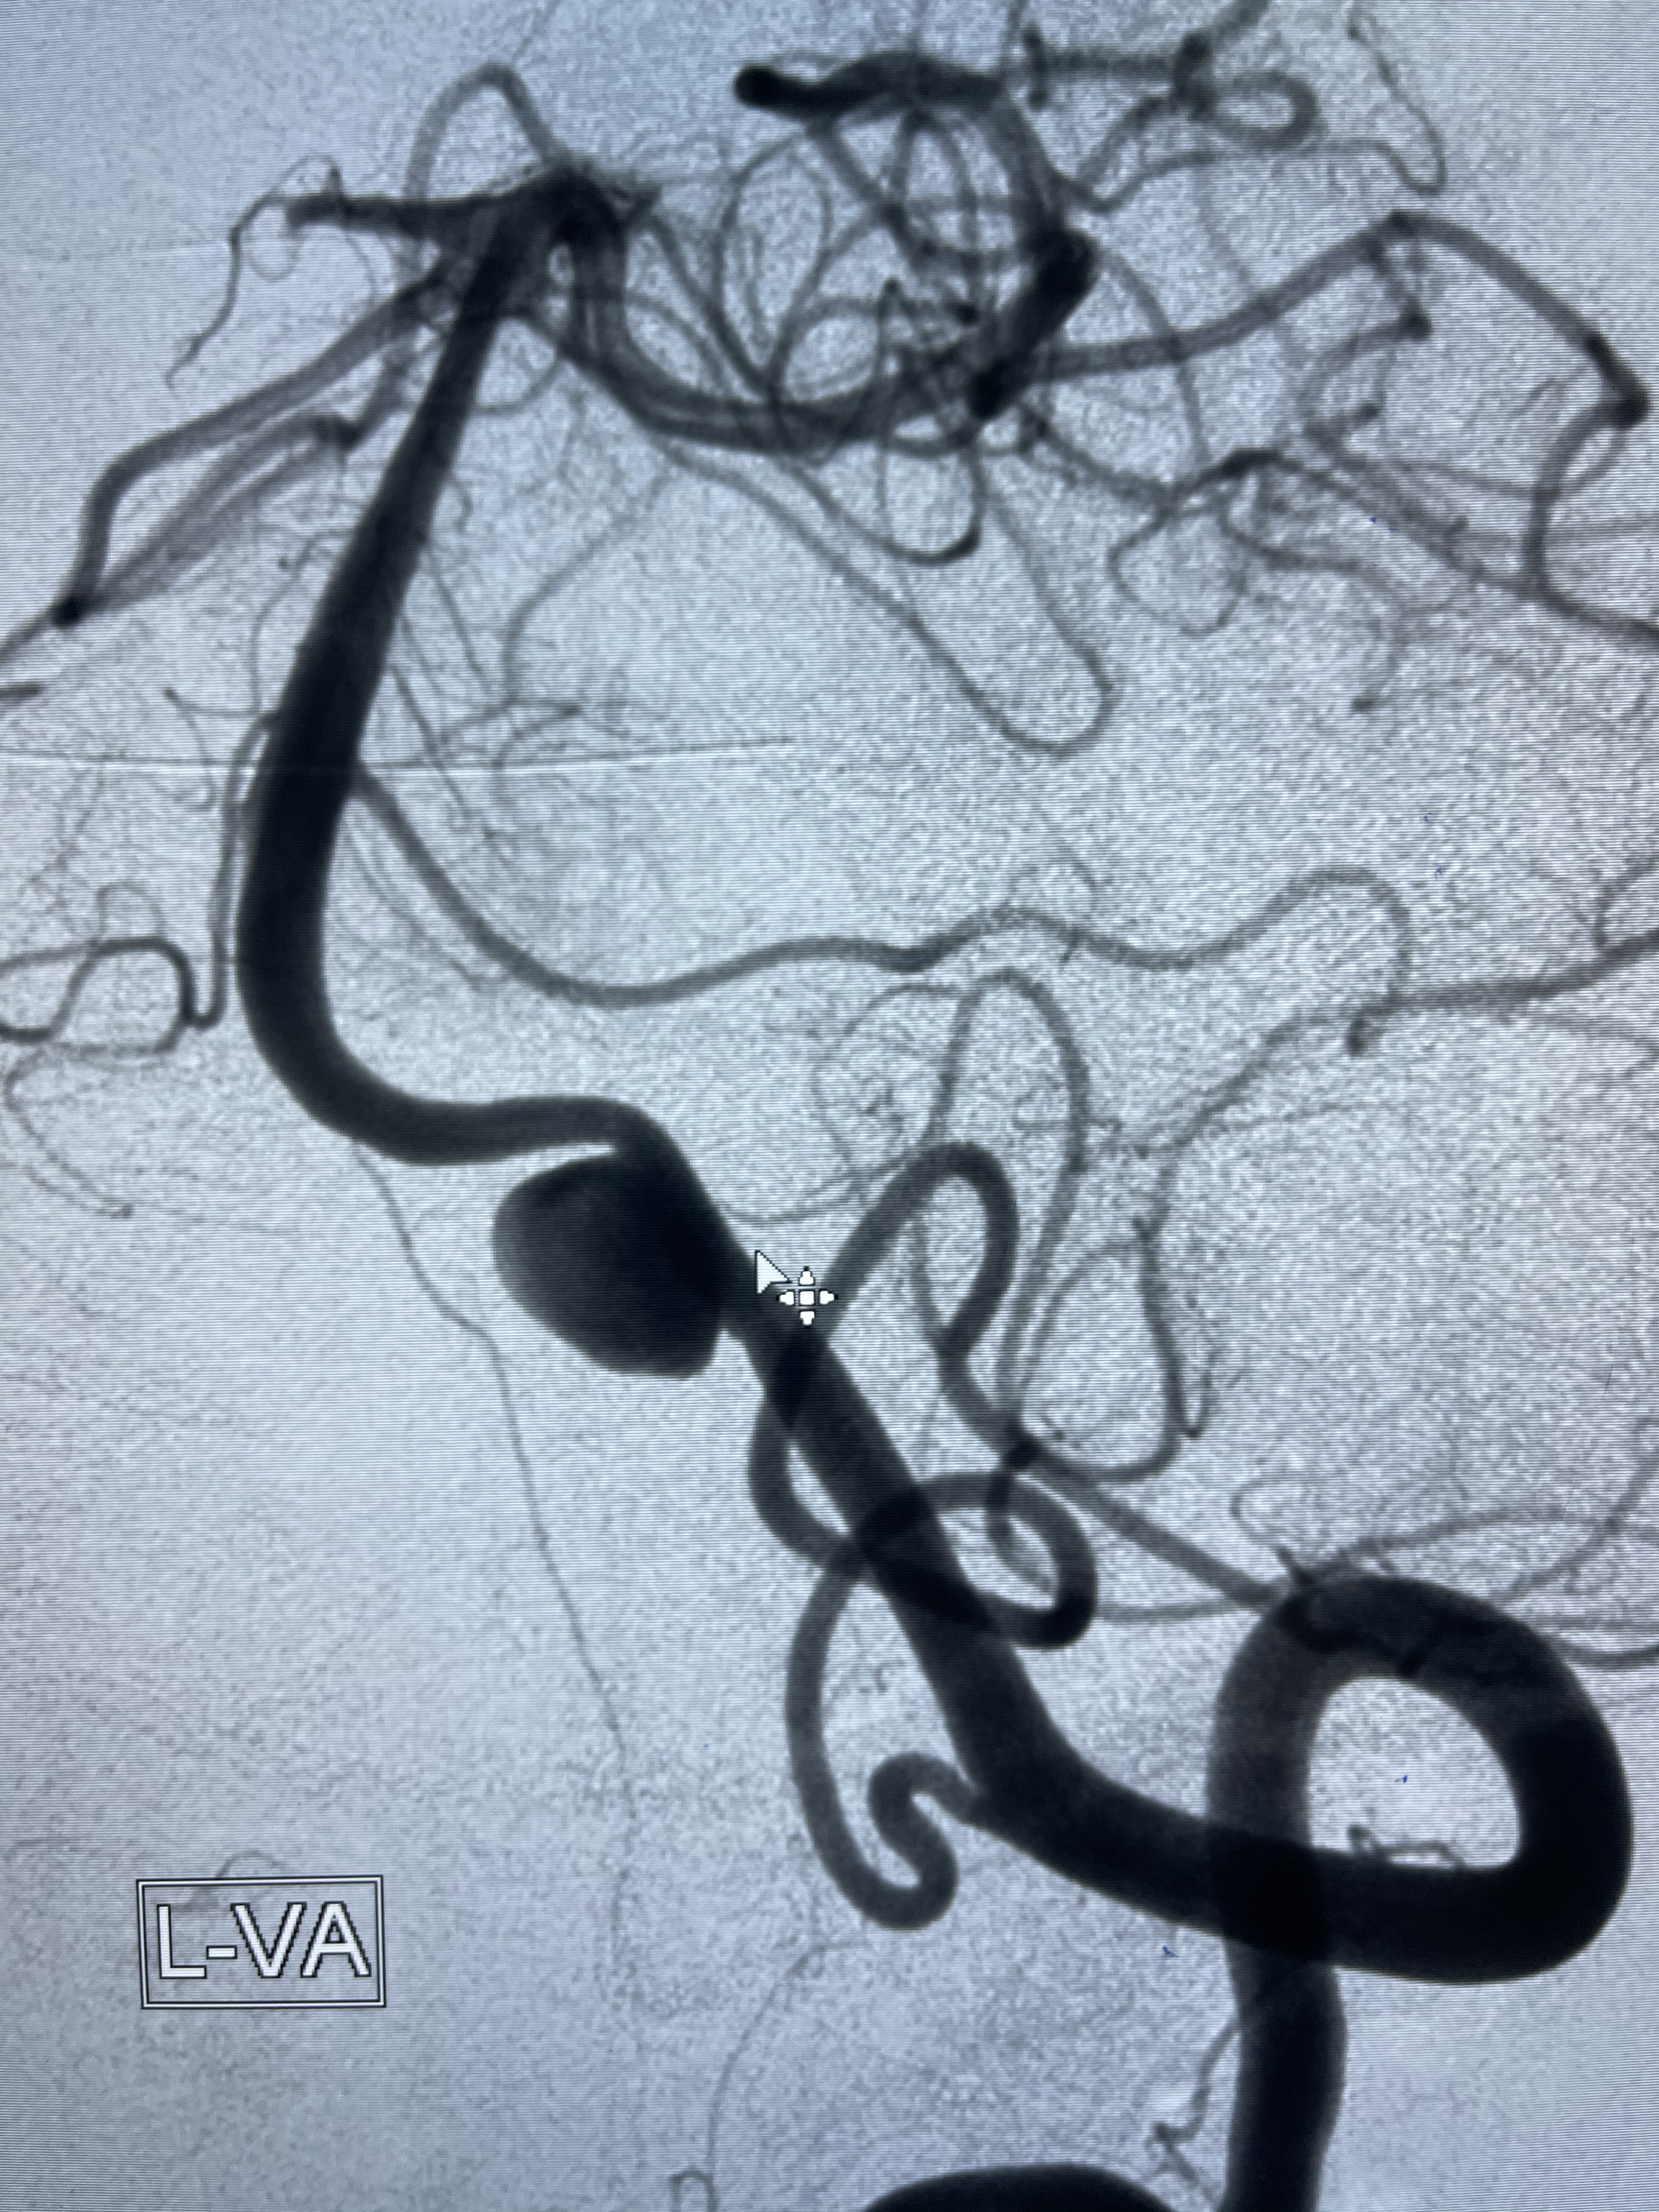

2021-03-08行全脑血管造影

左侧椎动脉V4夹层动脉瘤多支架辅助栓塞:

工作角度造影